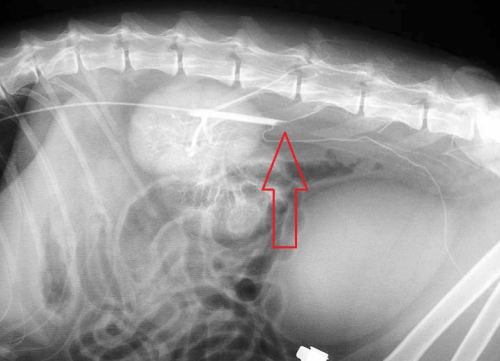

下の写真は筆者の経験した、若い猫で生じた原因のはっきりしない特発性の腹部大動脈血栓塞栓症での血管造影の写真です。赤矢印の先に白く見える造影剤が血栓によって欠けている部分がありますが、これはそれ以下への血行が完全に遮断されていることを示しています。腹部大動脈血栓塞栓症とはどういうものかということをご理解する上でのご参考としてご覧ください。

この写真の猫は心疾患や大きな合併症がみられなかっため、外科的に血栓を摘出して無事に回復しました。その後再発はなく、約7年後に悪性腫瘍のリンパ腫で生涯を全うするまでまで問題ない生活を送ることができています。ただし、血栓形成の原因となる心疾患などの予後の悪い病気を伴わず、外科手術が功を奏するケースは稀なものでしかありません。